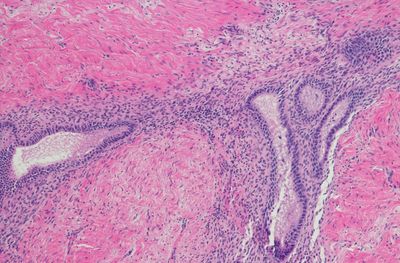

Often referred to as an "invisible illness," endometriosis remains poorly understood